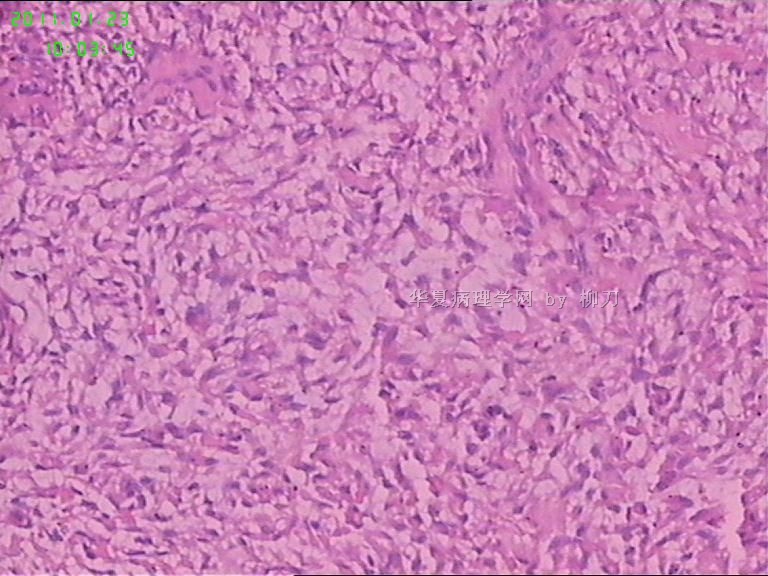

姓    名: ××× 性别:  男 年龄:  36

标本名称:  腮腺包块

简要病史:  包块2年多,数月来增大。

2,3图是前2个结节的镜下表现,梭形皮瓣是皮内痣。4以后是具完整包膜的肿块表现,核分裂少见。

我们考虑肌上皮瘤,少见多怪,老师们请多指教。

现有图像上看考虑肌上皮瘤。如果粘液样区域多,要考虑多形性腺瘤。

可以做一下组化:CK、SMA、S-100、GFAP、P63。

肌上皮瘤